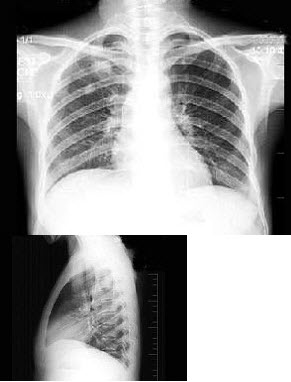

88、单项选择题

男,16岁,突感呼吸困难,大汗淋漓,胸片检查如图,最可能的诊断是()

A.右侧肺气肿

B.右侧肺部肿块

C.右侧气胸

D.右侧肺大泡

E.右侧肺挫伤

点击查看答案